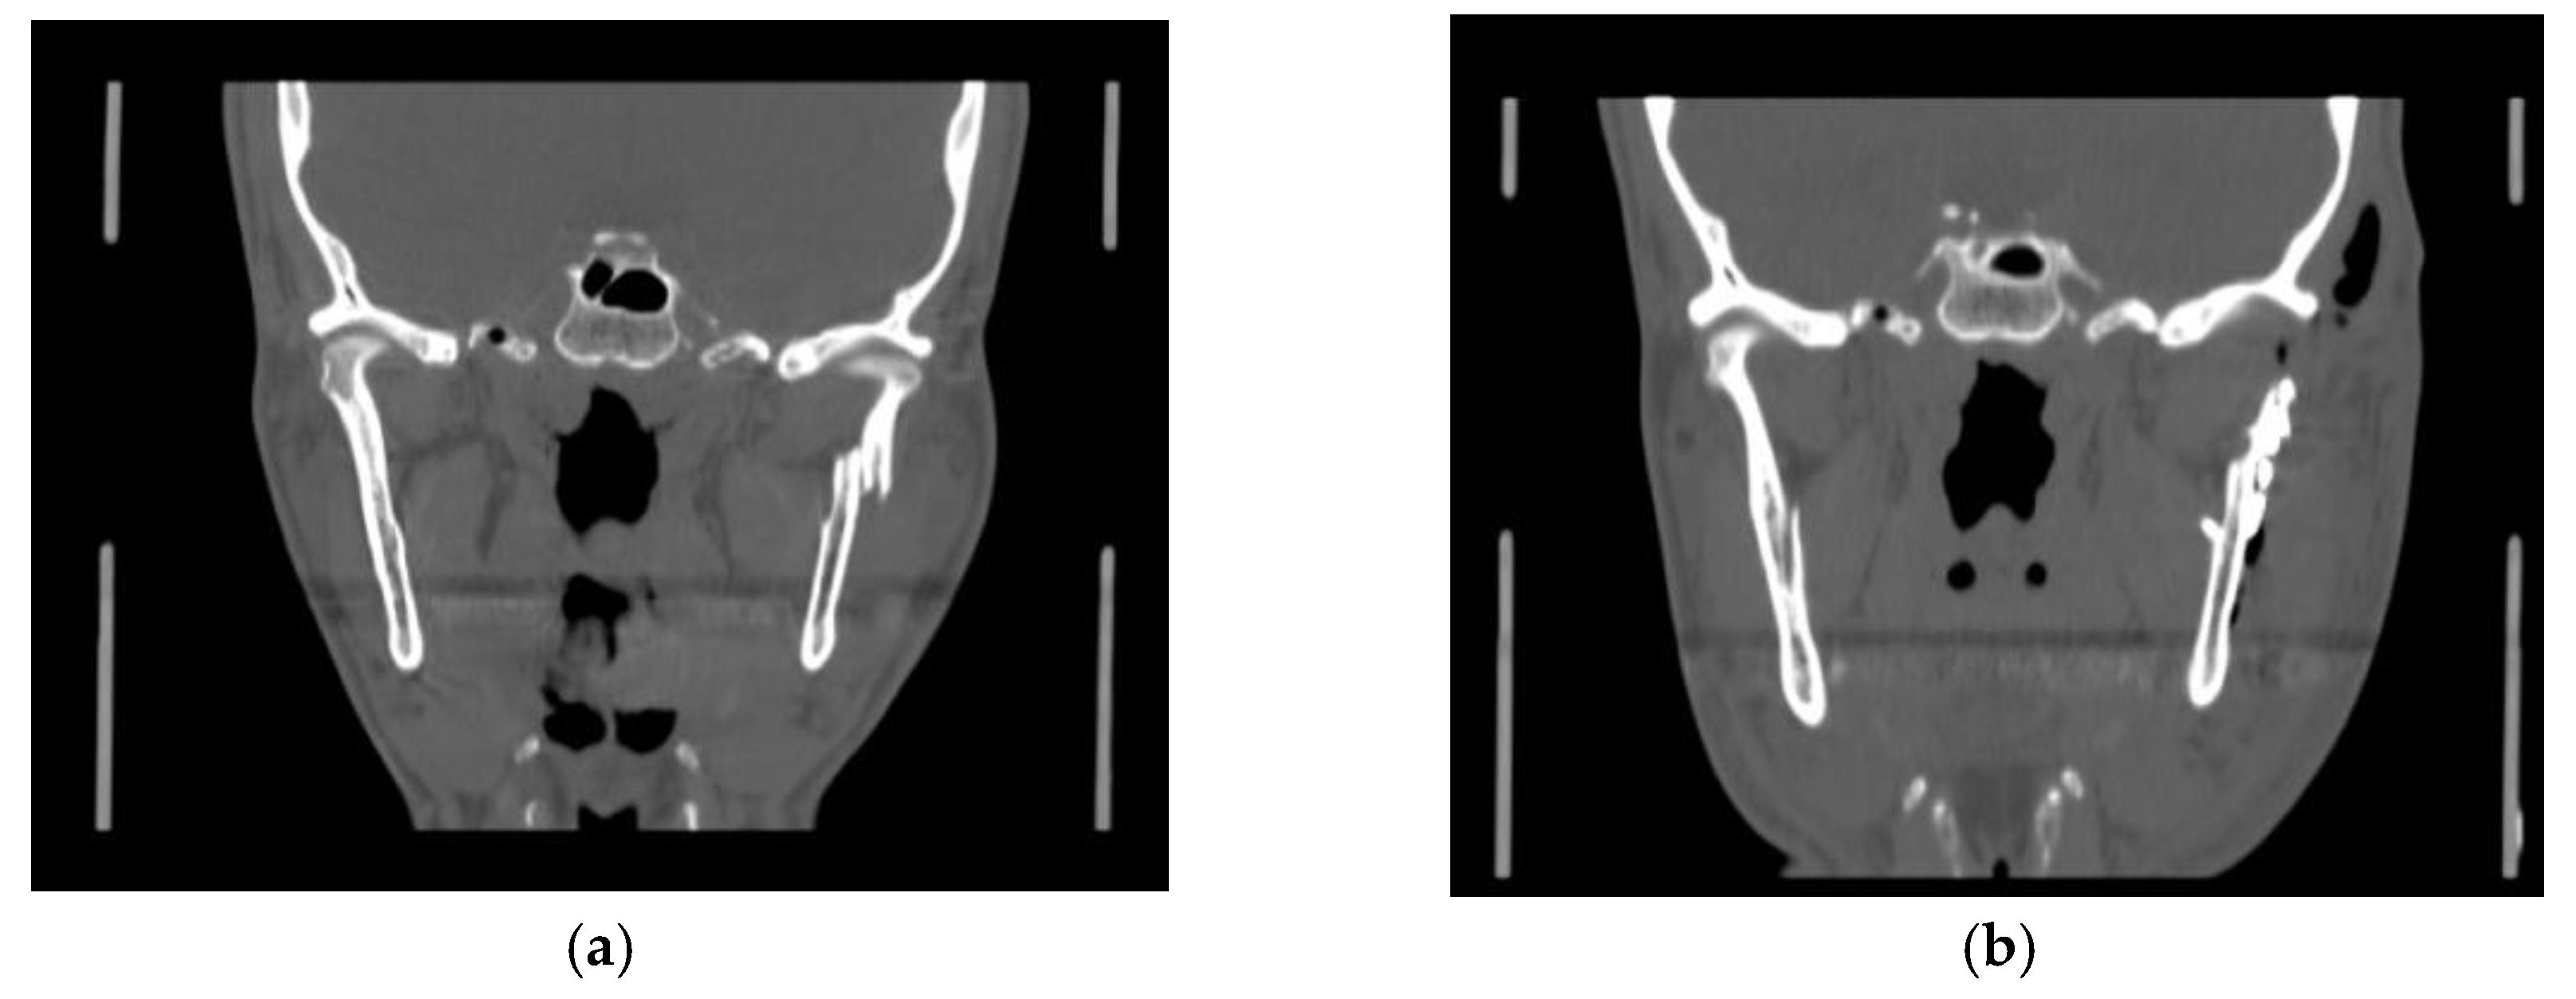

Surgical treatment was performed in patients with widely displaced fractures with lack of contact between the two fragments (Figure 1, Figure 2, Figure 3 and Figure 4), or when the displacement of the fragments caused a lack of function of the TMJ that could not be resolved with conservative treatments, or in multiple fractures of the middle third of the face in order to use the mandible as a guide for replacement of the bones of the middle third of the face, as previously described [8].

Figure 2. (a) Pre- operatory coronal CT scan; (b) post-operatory coronal CT scan of patient #2.